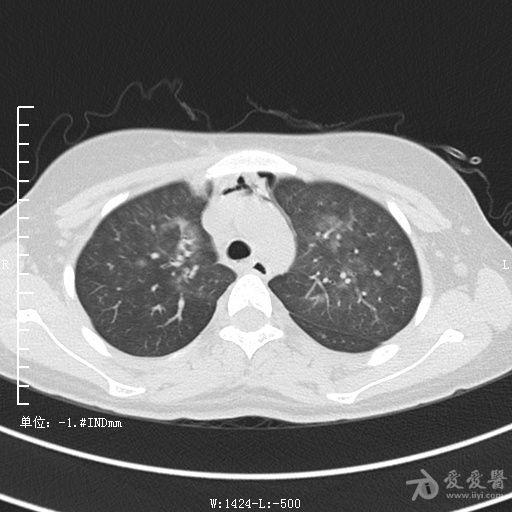

典型支气管扩张及肺水肿CT片

典型支气管扩张肺水肿